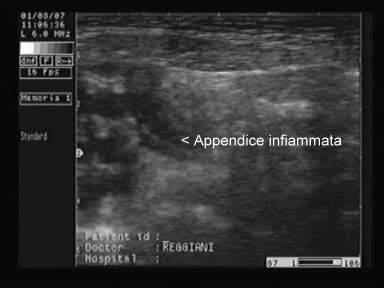

- Ecografia addominale: Rappresenta spesso il primo esame di imaging, specialmente nei bambini e nelle donne in età fertile, poiché è non invasiva e non espone a radiazioni. Può visualizzare l'appendice ingrossata e infiammata.